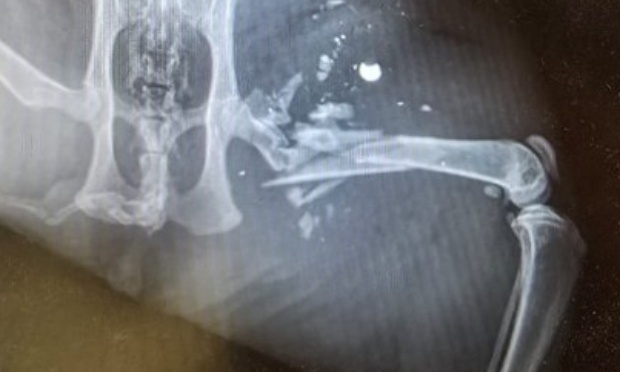

Notre chat Storm âgé de 2 ans, a été victime d’une blessure grave par arme à feu dans la journée du 12 juin 2025 dans la commune de Parleboscq dans les Landes (40310).L’os du fémur de la patte arrière gauche a éclaté sous l’impact du...